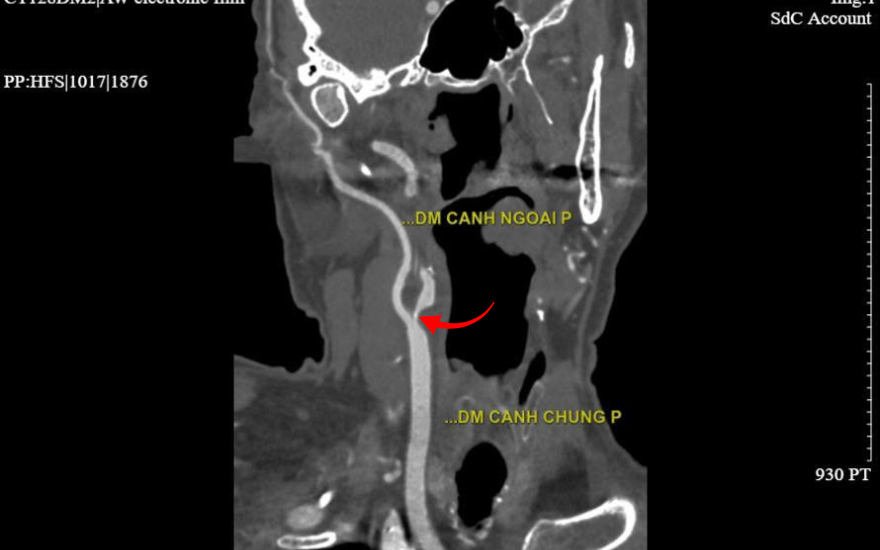

홍옥 푹즈엉밍 종합병원 심장 및 심혈관 중재술 과의 까오 마잉 훙(Cao Manh Hung) 전문의는 환자의 증상을 전형적인 일과성 뇌허혈 발작(TIA)으로 진단하고 뇌졸중 위험이 매우 높다고 판단했습니다. 정밀 검사 결과, 우측 내경동맥 입구가 90% 이상 협착되어 있었으며 다수의 죽상경화반이 발견되었습니다. 또한, 심장의 좌전하행지(LAD) 관상동맥 역시 90% 이상 협착된 상태였습니다.